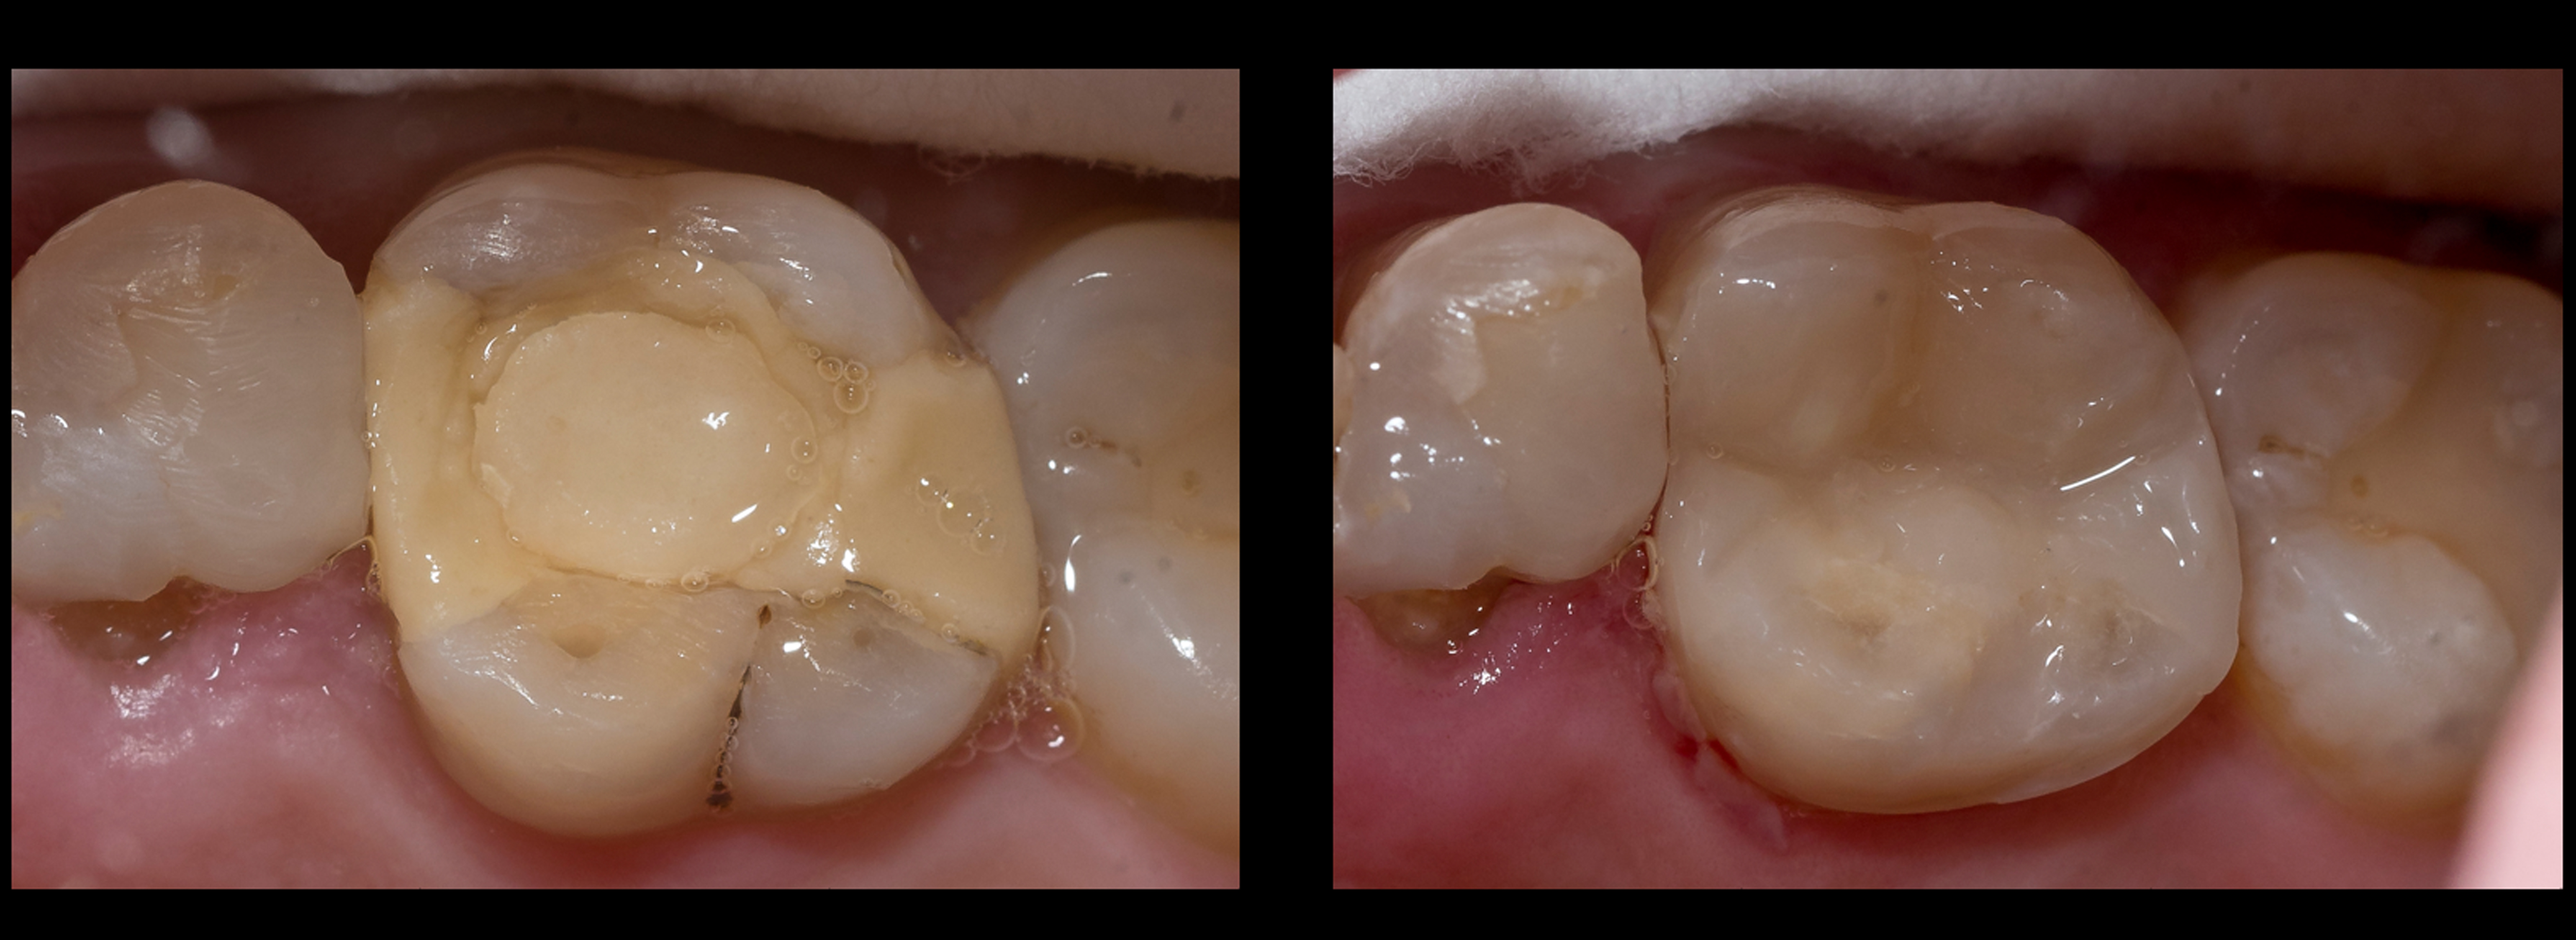

Z punktu widzenia pacjenta najważniejszym wyznacznikiem jakości wypełnienia, który może on łatwo skontrolować jest dopasowanie kolorystyczne materiału i tkanek zęba do siebie. Wypełnienie będzie uważane za „idealne” i estetyczne, jeśli będzie doskonale odtwarzało brakujący fragment zęba, a w tym odtworzeniu kolor gra rolę dominującą (5). Lekarze stomatolodzy wiedzą, że kształt wypełnienia oraz stopień jego polerowania ma równie duży wpływ na wrażenie dopasowania odbudowy do zęba co kolor materiału, ale dla pacjenta ogół wrażenia estetycznego koncentruje się zazwyczaj na kwestii kolorystycznej (6) (ryc. 1).

Ryc. 1. Gdyby pacjent mógł dokładnie obejrzeć wypełnienie w swoim zębie trzonowym, nie ma wątpliwości, które z nich uznałby za lepsze, bez względu na materiał z którego zostało wykonane.